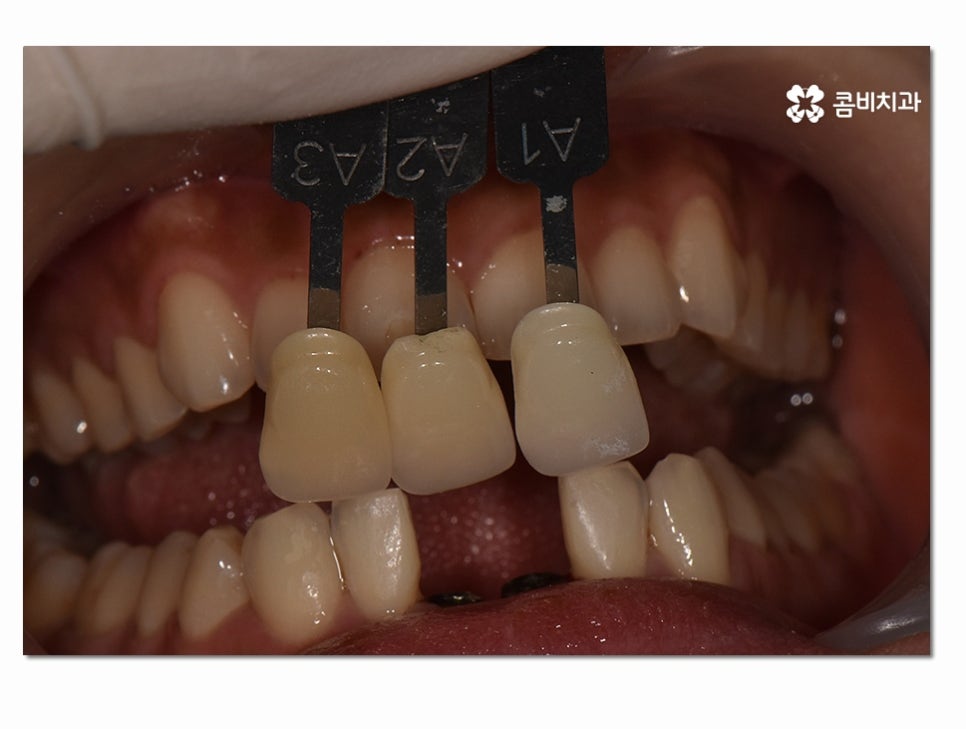

인공치근이 튼튼하게 자리를 잡게 된 것이 확인이 되면

보철물을 주변 치아의 색과 모양과 비슷하게 제작하여

결합하는 과정을 거치고 아랫니 임플란트 치료 과정이 마무리될 수 있어요.